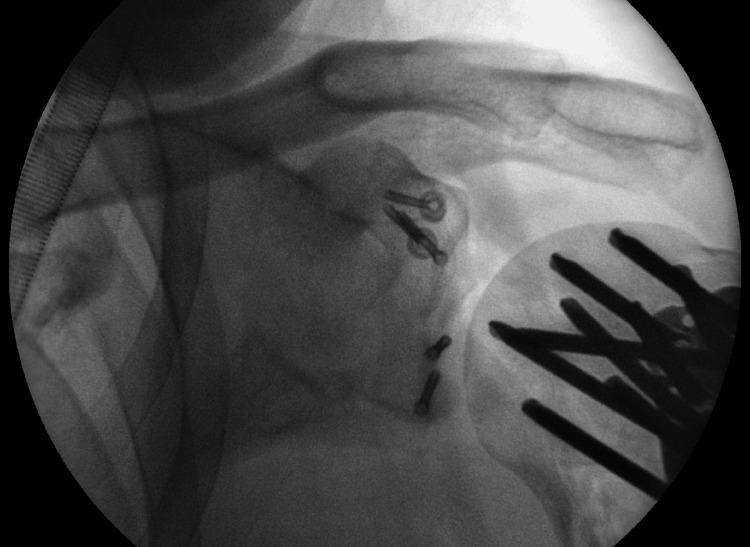

Fractures of the proximal humerus are common injuries with a bimodal age distribution. They usually present in younger patients after high-energy trauma and in elderly patients after lower-energy trauma. Fractures of the proximal humerus are rarely associated with concomitant fractures of the glenoid, and this is a complex injury pattern that indicates the presence of significant instability. Such injuries are usually treated surgically. Even more rarely, patients may present with proximal humerus fractures and fractures of the coracoid process. A male patient presented to our emergency department (ED) after a fall off the loading platform of his heavy goods vehicle (HGV), resulting in a right shoulder injury. During his initial assessment in ED, a computerised tomography (CT) scan demonstrated the presence of a comminuted proximal humerus fracture, a comminuted anterior glenoid wall fracture, and a coracoid process displaced fracture. Surgical fixation of all three fractures was undertaken in the same sitting. This is the first case described in the literature with a combination of the above injuries and serves as a reminder that as trauma complexity and incidence continue to increase, we should maintain a high index of diagnostic suspicion when dealing with such patients. Furthermore, we present our treatment approach for this case and the rationale behind it.

肱骨近端骨折是常见损伤,具有双峰年龄分布。它们通常在年轻患者遭受高能创伤后以及老年患者遭受低能创伤后出现。肱骨近端骨折很少与肩胛盂骨折同时发生,而这种复杂的损伤模式表明存在明显的不稳定。此类损伤通常采用手术治疗。更罕见的是,患者可能同时出现肱骨近端骨折和喙突骨折。一名男性患者从他的重型货车装载平台上跌落后来到我们的急诊科,导致右肩部受伤。在急诊科对他进行初步评估期间,计算机断层扫描(CT)显示存在肱骨近端粉碎性骨折、肩胛盂前壁粉碎性骨折以及喙突移位骨折。在同一次手术中对所有三处骨折进行了手术固定。这是文献中描述的首例上述损伤组合的病例,提醒我们随着创伤复杂性和发生率不断增加,在处理此类患者时应保持高度的诊断怀疑指数。此外,我们展示了针对该病例的治疗方法及其背后的原理。